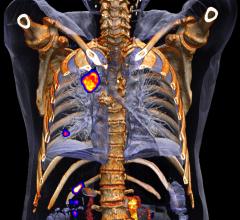

The last 12 months have seen significant growth in the positron emission tomography/computed tomography (PET/CT) segment of radiology, from both a manufacturing and a research perspective. One brand-new system received U.S. Food and Drug Administration (FDA) market clearance just months ago, while another started making its way into hospitals in the second half of last year. Several manufacturers also released software updates to help integrate PET/CT imaging into radiation therapy planning and execution. The increased interest was supported by several large studies exploring the advanced applications of PET/CT in oncology imaging.

In the world of molecular imaging, PET/MR is a wild card. But it’s a wild card that’s ready to be played. Three major vendors offer commercial products. The images are spectacular. So…what’s the hold up?